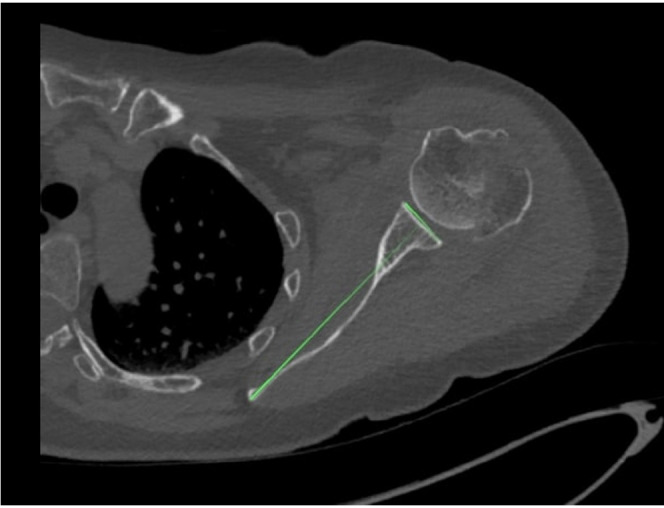

Methods: Shoulder CT scans for arthroplasty were analyzed retrospectively. Glenoid version was measured at the estimated glenoid midpoint using unformatted and formatted 2D-CT in the scapular plane. Measurements from 3D-CT reconstructions using the Corrected Friedman Method were used as the control. Inter- and intra-observer reliability was calculated as well as minimally detectable difference.

Results: Sixty-five CT scans were analyzed (mean age, 61.7 years). Mean glenoid version was -3.48° (standard deviation [SD], 8.7°) on unformatted 2D-CT, -3.27° (SD, 8.15°) on formatted 2D-CT, and -4.25° (SD, 7.92°) on 3D-CT. Although no significant difference in mean values was observed (analysis of variance, P=0.245), formatted 2D-CT measurements were within 6° of 3D-CT in 95.4% of cases versus 83.1% for unformatted 2D-CT (P=0.023). Directional error occurred in 27.7% of unformatted scans and 16.9% of formatted scans. Inter-observer reliability was highest for 3D-CT (intraclass correlation coefficient [ICC]=0.83; 95% CI, 0.74-0.89), and intra-observer agreement was strongest for 3D-CT (ICC=0.91; 95% CI, 0.86-0.94), followed by formatted 2D-CT (ICC=0.83; 95% CI, 0.73-0.89) and unformatted 2D-CT (ICC=0.77; 95% CI, 0.65-0.85).

Conclusions: 3D-CT reconstructions are widely considered the most accurate and reproducible method for glenoid version assessment, supported by multiple comparative imaging studies. Formatted 2D-CT provides a reliable alternative when 3D-CT is unavailable, significantly outperforming unformatted 2D-CT in both agreement with the 3D reference and intra- and inter-observer reliability. Level of evidence: IV.